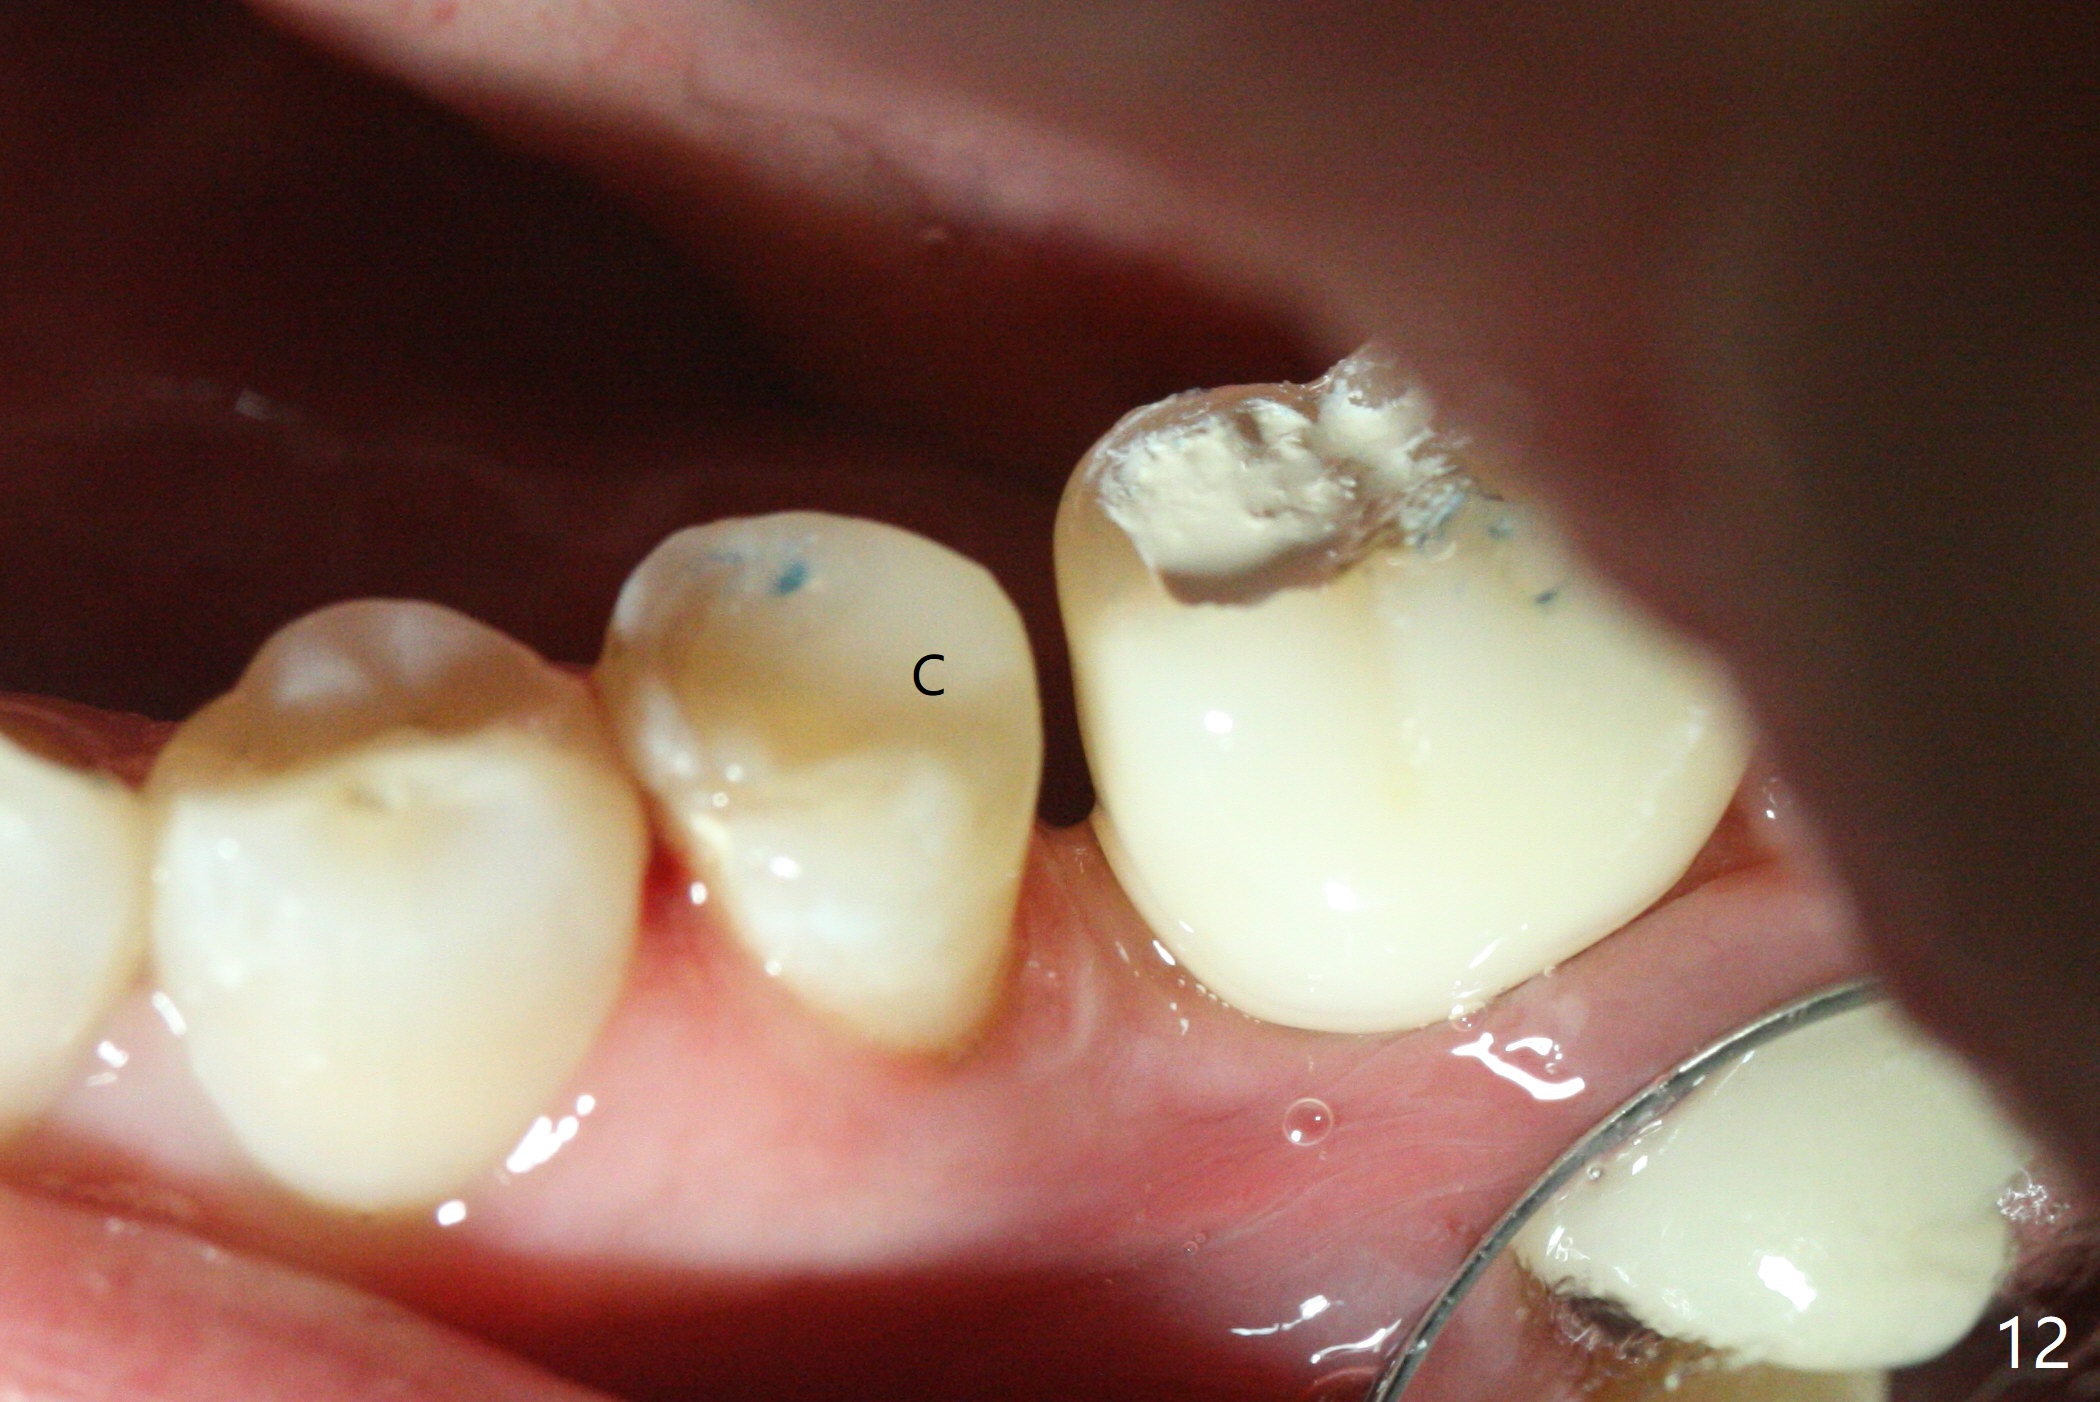

With 34 mg of Lidocaine and 17 mcg of Epinephrine (local infiltration), a 4.5x8.5 mm implant is placed with guide. The insertion torque is ~50 Ncm. It is placed in precise depth and in a short period of time (tolerable to the operators and patient, easier than mini-implant placement, Fig.1). There is no postop pain or paresthesia. The mesidistal position is within treatment plan (Fig.2). Miniimplants are placed to intrude #14 14 days prior. The teeth #16,17 and 32 are extracted 3 months postop. Minimal bone resorption at the crest is noted nearly 4 months postop (Fig.3). Bands and brackets are placed #18 upright 4 months postop (Fig.4 (14 niti wire)). The buccal and lingual view of the preop model shows that the supraerupted 1st molar (#14) has close relationship with the distal surface of the tooth #20 (Fig.5,6), accounting for the severe wear of the latter (Fig.8-11). The implant not only acts as an anchor to upright #18 in 4.5 months post banding (Fig.7 *), but also as an occlusal stop so that #18 has no interference to be moved. The stress on the implant results in radiating trabecular pattern (Fig.7,11 (9,11 months postop), as compared to before loading (Fig.1,3)). Restoring the distal contour of #20 with composite (Fig.12 C) makes it easy to close the space by adding porcelain the mesial surface of the implant crown. The crown/abutment is loose in China 7 months post cementation.